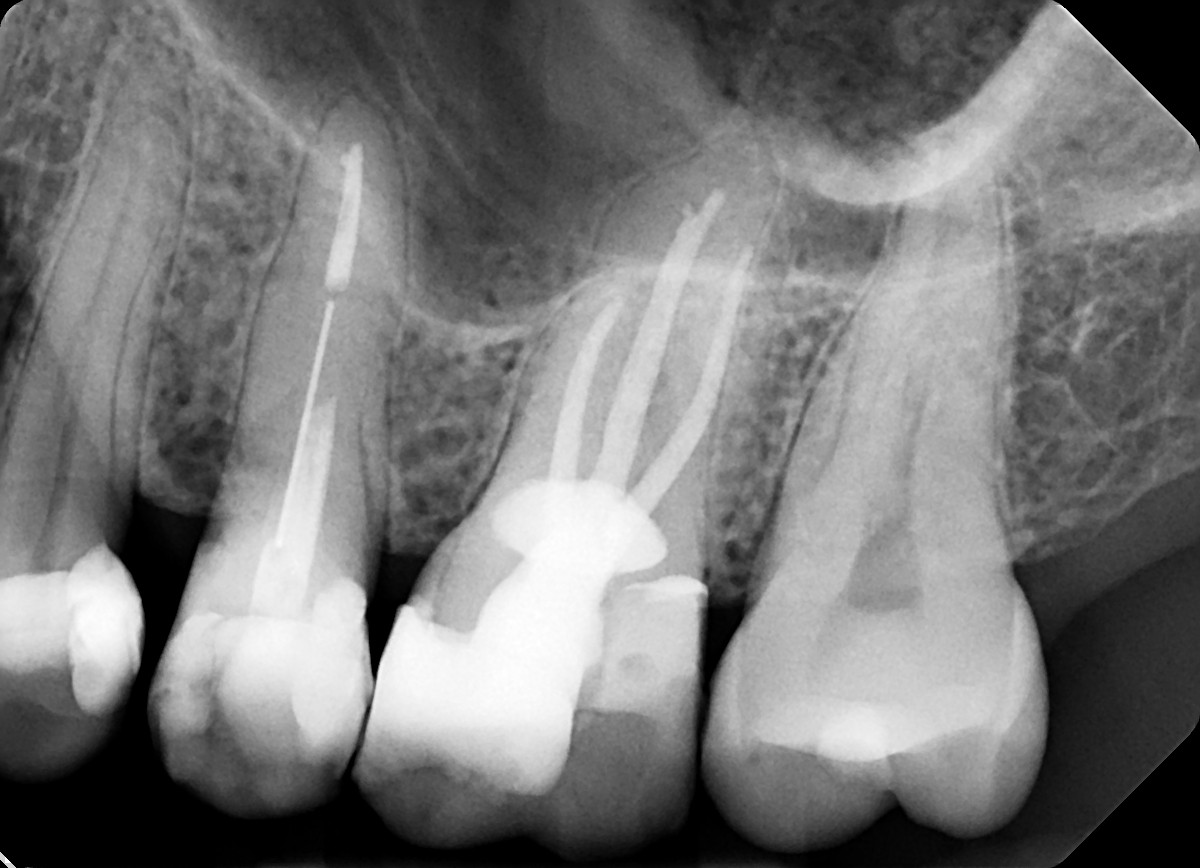

19 / 35

19. On which surface a recurrent caries can be detected?

This is the PA X ray of the question # 18, based on this X ray recurrent X ray for distal tooth # 3.7 can also be selected